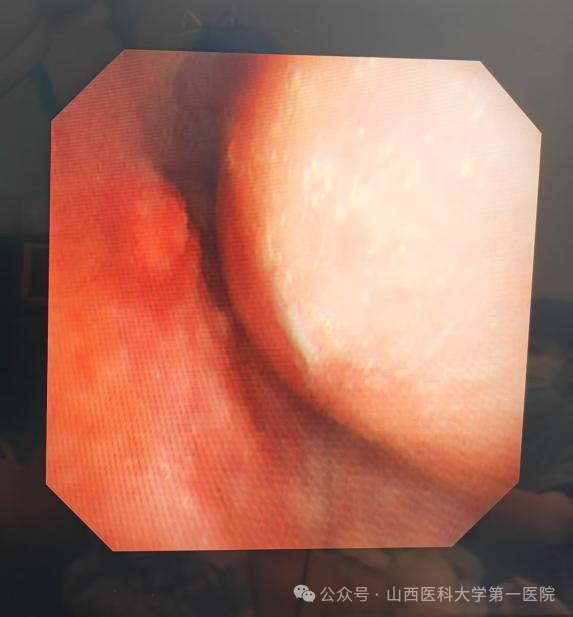

呼吸介入治疗后管腔通畅

5月10日下午,重症医学科高海晋医生敏锐察觉到患者血氧饱和度下降,呼吸与危重症医学科呼吸介入团队得知情况后快速响应,尹建升医生与李艳青护士为患者行床旁支气管镜检查,发现气管支架移位,这是气管支架置入术后的常见并发症,经过调整后支架重新支撑起气管狭窄部位。

5月12日,甲状腺外科刘静主任团队顺利为患者切除甲状腺肿物(病理提示右侧甲状腺恶性肿瘤),郭志宏主任医师、刘翔医生为患者取出气管支架,气管彻底恢复通畅,经过密切观察,患者一般情况平稳,于5月21日顺利出院,等待病理结果决定下一步治疗策略。